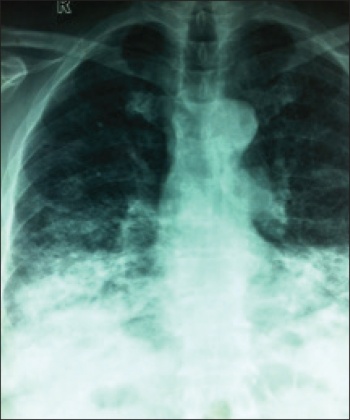

Figure 4. CXR three weeks later showing extensive bi-basal involvement

Figure 4. CXR three weeks later showing extensive bi-basal involvement (click to enlarge)

Meanwhile, another CXR was done three weeks later (see Figure 4) which showed the extensive bi-basal involvement.

A second opinion was sought and the patient was sent for endobronchial ultrasound-guided (EBUS) biopsy, which revealed the final histology of lepidic adenocarcinoma of bronchoalveolar type.